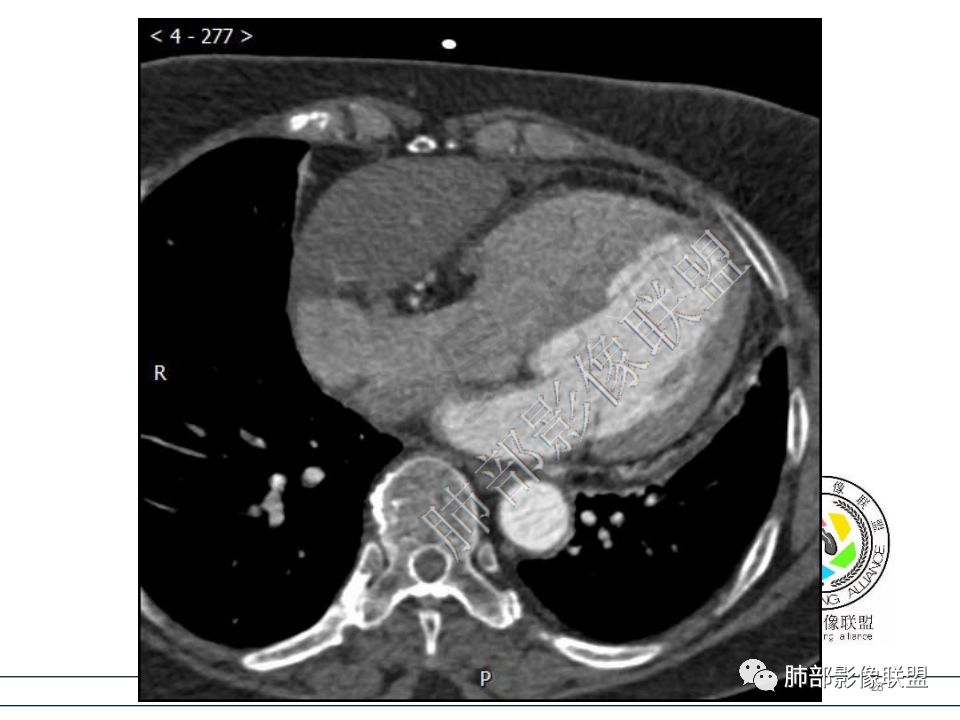

病例一考虑心包来源,病灶从大动脉根部一直延续到心底,明显不均匀强化,没有心包积液,良性?边缘强化,良性先考虑血管瘤。 医学百科网 | YxBaike.Com

病变位于心包,密度较低,边缘结节性强化,猜一个血管瘤。

定位心包,局部与右心房分界不清,右心房受压,冠脉受压,渐进性强化,没有心包积液,考虑心包来源或右心房游离壁来源血管瘤。 医学百科网 | YxBaike.Com

从心底沿右侧房室沟一直延伸至近膈面,心包来源可以解释的通;另外病变与右心室右心房之间的脂肪间隙一直存在。

心包海绵状血管瘤的CT特征为平扫呈边界清楚的圆形或者类圆形低密度肿块,对比增强扫描是诊断海绵状血管瘤的关键。动脉期肿瘤边缘可出现散在斑片状、结节状明显强化灶,接近同层强化大血管密度。静脉期散在的强化灶相互融合同时向肿瘤中央扩展。

渐进性强化,边界清晰,周围脂肪间隙存在,没有心包积液。

边界清晰,周围脂肪间隙存在,临近器官受压无受累。

心包海绵状血管瘤 医学百科网 | YxBaike.Com